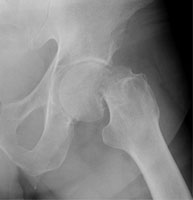

Femoral neck fractures also result from falls, especially in elderly and osteoporotic females. They are associated with radial and humeral fractures. The Garden classification is widely used to categorize these fractures. Garden I is an incomplete fracture through the femoral neck while with Garden II, the fracture is complete. With Garden III fractures, there is impaction, and with Garden IV, the femoral neck is superiorly migrated relative to the femoral head. Garden IV fractures have the highest risk of avascular necrosis.

D | Lateral view of a Garden IV fracture. |